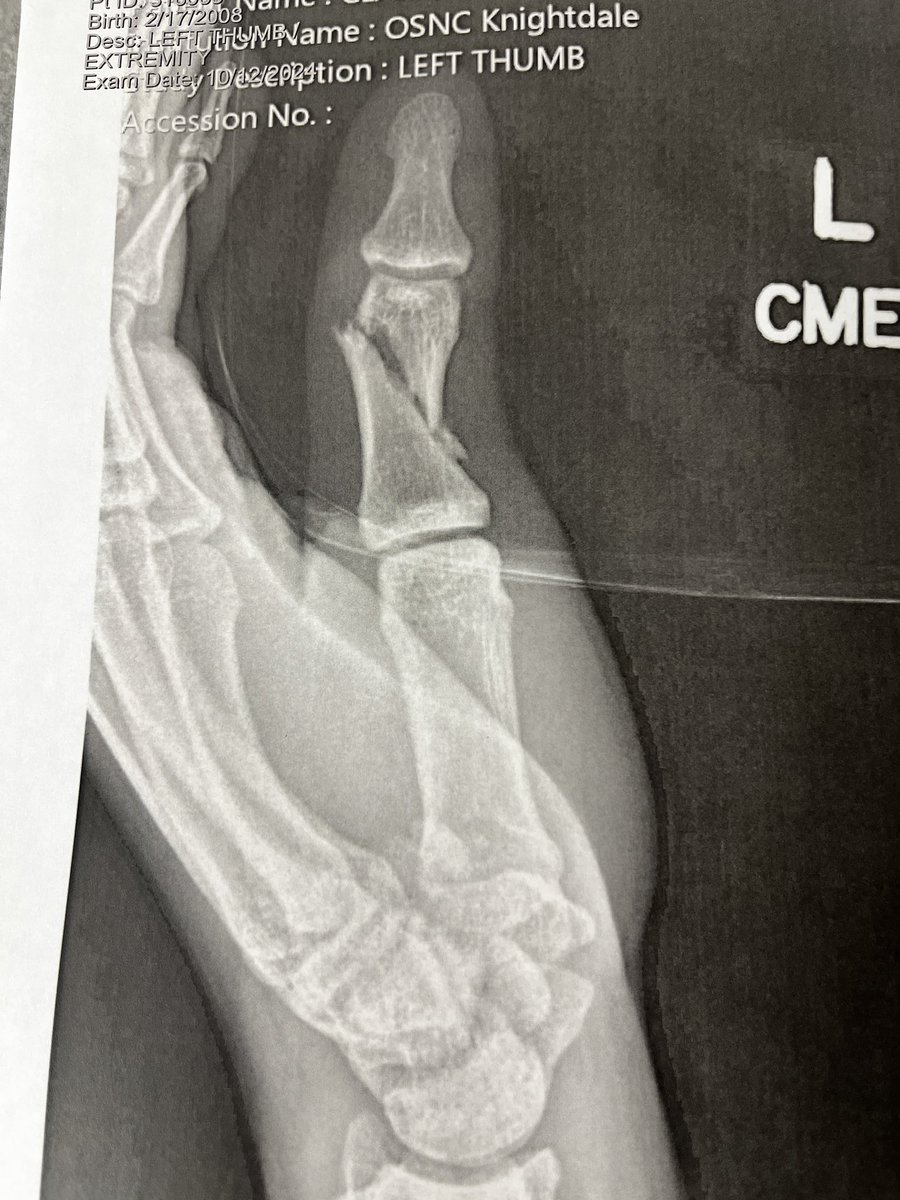

Glade to start the season 100 percent this year after a horrible hand injury and surgery,really thankful to all my coaches and trainers who all helped Enloe Football